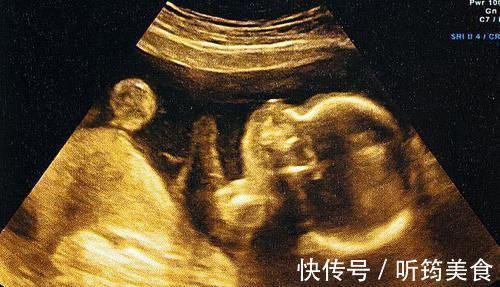

2、B超技术尚不完善

别看现在B超使用率很高,感觉技术相当成熟的样子,其实行内人都知道,它的问题极多,比如最关键的一条:成像模糊。